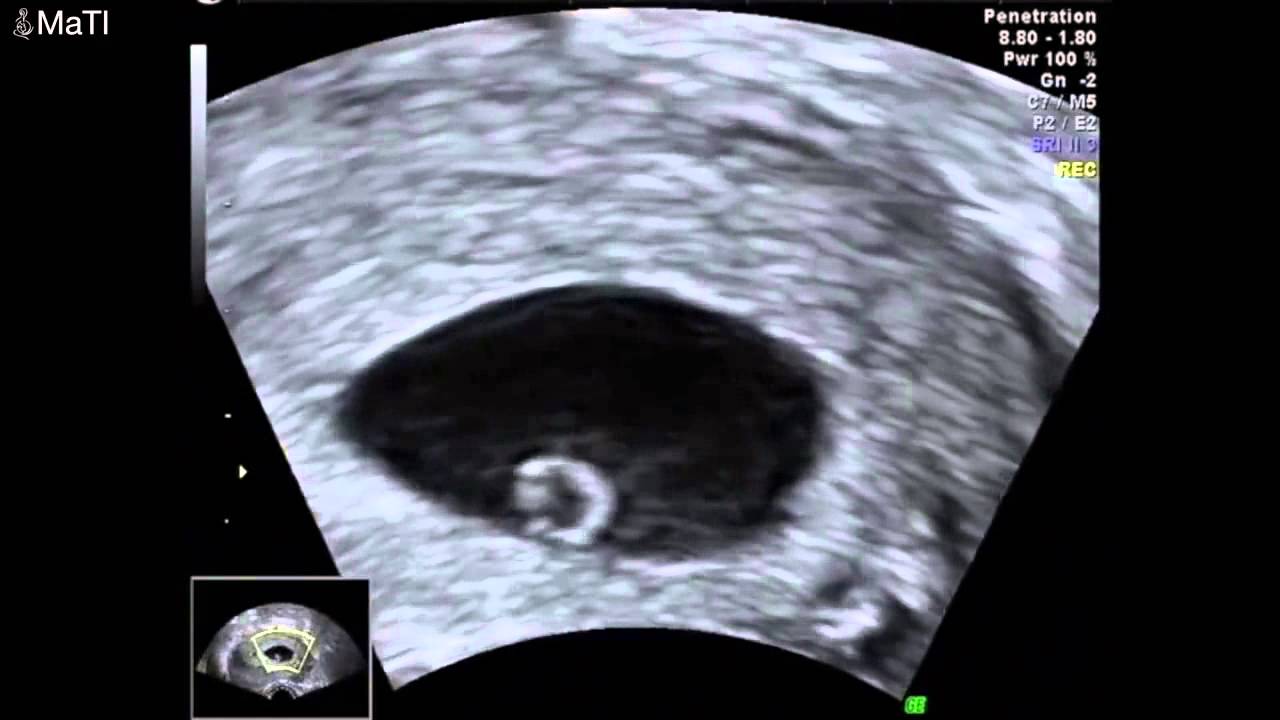

Haftasında annede meydana gelen değişimler hamileliğin ilk haftalarındaki belirtilere ek olarak 9. 34 haftalik bebek ultrason görüntüsü üç veya dört boyutlu ultrason gebeliğin ilk aylarından itibaren yapılabilmektedir. 9 haftalık bir gebelikte bebek, ultrasonda rahatlıkla görülebilecek boyuta ulaşmıştır. Dokuz haftalık gebelikte bebeğin boyu yaklaşık 2 cm, ağırlığı 2 gram kadardır. Dokuzuncu hafta bebek gelişimi ayrıntılı ultrason videosu. Haftada bebek hareketleri devam eder, bebek hareket ettikçe kasları güçlendir.

Anne karnındaki 9 haftalık bebeğin görüntüsü. Dokuz haftalık gebelikte bebeğin boyu yaklaşık 2 cm, ağırlığı 2 gram kadardır. 34 haftalik bebek ultrason görüntüsü üç veya dört boyutlu ultrason gebeliğin ilk aylarından itibaren yapılabilmektedir. 9 haftalık bir gebelikte bebek, ultrasonda rahatlıkla görülebilecek boyuta ulaşmıştır. Kalp kapakları, burun ucu ve retina tabakası da 9. Haftada bazı annelerde varis ve basur şikayetleri görülebilir.

9 haftalık bir gebelikte bebek, ultrasonda rahatlıkla görülebilecek boyuta ulaşmıştır. 9 haftalık bebek ultrasonda başı her zamanki gibi göğsüne ve karnına doğru durur. Ayakları vücudunun ortasına doğru yaklaşıyor.

9 haftalık bebeğin ultrason görüntüsü 9 haftalık bebek ultrason görüntüsü incelendiğinde ellerini kalbinin üzerinde birleştirdiği görülebilir. Son adet tarihine göre 9. 9 haftalık gebelik hamilelik görüntüsü 10 şub 2017.

9 haftalık bir gebelikte bebek, ultrasonda rahatlıkla görülebilecek boyuta ulaşmıştır. Bu hareketler 9 haftalık bebeğin ultrason görüntüsünde seçilebilir. Gözler gelişir, dil oluşmaya başlar.

Elleri, bilekten kıvrılarak kalbinin üst kısmında duruyor. Ama minik tekme ve yumruklarını senin hissedebilmene. 9 haftalık gebelik ultrason görüntüsünde bebeğinizin gözlerinin net bir şekilde göründüğünü fark edebilirsiniz.

9 haftalık gebelik ultrason görüntüleri; 9 haftalık bebek ultrasonda başı her zamanki gibi göğsüne ve karnına doğru durur. Bu haftalar bebeğinizin kollarının ve bacaklarının uzamaya devam ettiği haftalardır.

Bu hafta bebeklerin başı henüz eğik durur ve yuvarlaklaşmaya başlar. Bu hareketler 9 haftalık bebeğin ultrason görüntüsünde seçilebilir. Onuncu haftada bebek bütün organ sistemleri gelişmiş olduğu için artık embriyo değil fetus olarak adlandırılır ve bu hafta fetal dönemin başlangıcıdır.

Haftada bazı annelerde varis ve basur şikayetleri görülebilir. Bebeğinizin ayakları vücudunun ortasına doğru yaklaşmış ve c harfi görüntüsü ile neredeyse bir insan görünümüne ulaşmıştır. 9 haftalık gebelik ultrason görüntüsünde bebeğinizin gözlerinin net bir şekilde göründüğünü fark edebilirsiniz.

9 haftalık bebeğin ultrason görüntüsü nasıl olur

Haftasında annede meydana gelen değişimler hamileliğin ilk haftalarındaki belirtilere ek olarak 9. Haftada bebek hareketleri devam eder, bebek hareket ettikçe kasları güçlendir. 9 haftalık bebek görüntüsü 9 haftalık bebeğin ultrason görüntüsü incelenirken net şekilde kolların ve bacakların uzamaya başladığı görülebilir.

Bu hareketler 9 haftalık bebeğin ultrason görüntüsünde seçilebilir. Bu haftalar bebeğinizin kollarının ve bacaklarının uzamaya devam ettiği haftalardır. Başının biraz daha yuvarlak hale geldiği görülebilir.

9 haftalık bebek ultrasonda başı her zamanki gibi göğsüne ve karnına doğru durur. Gebelikte 9.hafta tamamlanması ile embriyo olarak tanımlanan bebek fetus olarak ifade edilmeye başlar. Bebeğin artık vücudunu, kol ve bacaklarını hareket ettirebilir hale gelir.